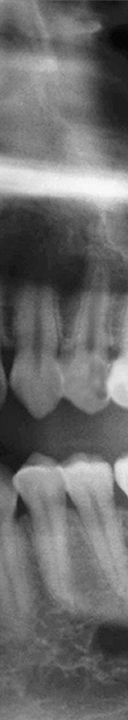

어렸을 때 부터 우리는 치아 건강의 중요성에 대해 어른들께서 하시는 말씀을 들으며 자라고 양치를 꼼꼼히 하는 법을 배우며 치아를 건강하게 관리하기 위해 노력하고 있었어요. 6-7살부터 치아가 빠지기 시작하여 초등학교 저학년부터 영구치가 나오기 시작하여 총 28개의 치아가 자라게 되었어요. 다른 치아가 모두 자란 후 마지막으로 맹출하는 치아인 사랑니는 10대 후반에서 20대 초에 자라게 되며 자라는 시기도 사람마다 차이가 있지만 사랑니의 개수도 상악과 하악 각각 2개씩 총 4개가 자라는 경우도 있고 1-2개만 자라거나 아예 맹출하지 않는 경우도 있었어요. 이처럼 사랑니는 사람에 따라 자라는 시기, 개수, 자라는 유형 등 차이가 많이 있었어요. 사랑니는 큰 어금니 중에서도 세번째에 위치하고 있어 제 3대구치라고 부르기도 하며 한참 전의 과거에는 불을 사용하지 못해 질긴 음식을 주로 먹게 되어 사랑니를 제 2의 어금니처럼 이용하였지만 현대 사회가 진행될 수록 부드러운 음식을 섭취하게 되어 강한 치악력이 필요하지 않게 되었어요. 많이 사용하지 않기 때문에 점점 턱뼈가 퇴화하게 되었고 그로 인해 사랑니가 자라날 공간이 부족하게 되고 사랑니가 반듯하게 자라지 않고 비스듬하게 자라거나 잇몸 안에 매복 되어 자라는 경우가 많았어요.

또한 사랑니가 삐뚤어지게 자라거나 매복 되어 있는 경우에는 더욱 더 심각한 문제를 일으킬 수 있었어요. 올바르게 자라지 않아 정상적으로 위치하고 있는 주변 치아에 영향을 주게 되어 치아 배열이 불규칙해질 수 있으며 또한 수평으로 누워서 잇몸에 완전히 덮여 사랑니가 아예 보이지 않는 경우, 또는 일부분만 덮여 있는 부분 매복처럼 다양한 형태로 나타날 수 있었어요. 사랑니가 매복 되어 있는 경우에는 염증이 생길 수 있어 볼, 편도선, 림프절 등이 부어올라 극심한 통증을 느끼게 되었어요. 또한 매복 되어 있는 사랑니의 형태가 심각한 경우에는 턱 뼈의 변형까지 생길 수 있었어요.

신논현역치과에서는 3D CT 장비로 촬영을 하여 사랑니의 매복 상태와 사랑니 부근의 신경처럼 중요한 부분을 정밀 검사를 통해 확인하고 사랑니 발치에 대한 안전한 치료 계획을 세운 후 발치를 진행하고 있었어요. 개인 구강의 상태에 따라 사랑니의 모양, 매복 형태 및 정도가 모두 다르기 때문에 아름드리에서는 그에 알맞는 방법으로 사랑니 발치를 환자 구강 상태에 맞게 진행하고 있었어요.